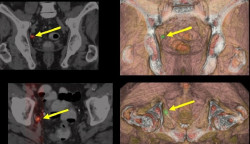

El Hospital Santa Clotilde de Santander ha inaugurado este viernes un nuevo servicio de diagnóstico por imagen, único en Cantabria, con el que añade a sus instalaciones la última tecnología en imagen médica a través de inteligencia artificial (IA), y que también incluye una unidad específica para la mujer.